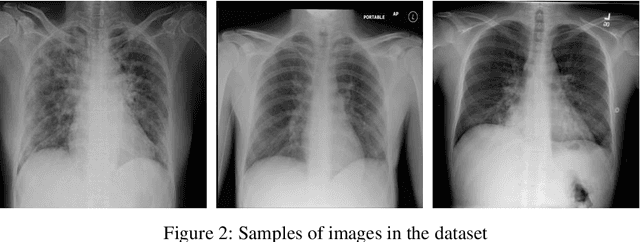

Abstract:The COVID-19 disease was first discovered in Wuhan, China, and spread quickly worldwide. After the COVID-19 pandemic, many researchers have begun to identify a way to diagnose the COVID-19 using chest X-ray images. The early diagnosis of this disease can significantly impact the treatment process. In this article, we propose a new technique that is faster and more accurate than the other methods reported in the literature. The proposed method uses a combination of DenseNet169 and MobileNet Deep Neural Networks to extract the features of the patient's X-ray images. Using the univariate feature selection algorithm, we refined the features for the most important ones. Then we applied the selected features as input to the LightGBM (Light Gradient Boosting Machine) algorithm for classification. To assess the effectiveness of the proposed method, the ChestX-ray8 dataset, which includes 1125 X-ray images of the patient's chest, was used. The proposed method achieved 98.54% and 91.11% accuracies in the two-class (COVID-19, Healthy) and multi-class (COVID-19, Healthy, Pneumonia) classification problems, respectively. It is worth mentioning that we have used Gradient-weighted Class Activation Mapping (Grad-CAM) for further analysis.

Abstract:The Coronavirus was detected in Wuhan, China in late 2019 and then led to a pandemic with a rapid worldwide outbreak. The number of infected people has been swiftly increasing since then. Therefore, in this study, an attempt was made to propose a new and efficient method for automatic diagnosis of Corona disease from X-ray images using Deep Neural Networks (DNNs). In the proposed method, the DensNet169 was used to extract the features of the patients' Chest X-Ray (CXR) images. The extracted features were given to a feature selection algorithm (i.e., ANOVA) to select a number of them. Finally, the selected features were classified by LightGBM algorithm. The proposed approach was evaluated on the ChestX-ray8 dataset and reached 99.20% and 94.22% accuracies in the two-class (i.e., COVID-19 and No-findings) and multi-class (i.e., COVID-19, Pneumonia, and No-findings) classification problems, respectively.

Abstract:The new coronavirus (known as COVID-19) was first identified in Wuhan and quickly spread worldwide, wreaking havoc on the economy and people's everyday lives. Fever, cough, sore throat, headache, exhaustion, muscular aches, and difficulty breathing are all typical symptoms of COVID-19. A reliable detection technique is needed to identify affected individuals and care for them in the early stages of COVID-19 and reduce the virus's transmission. The most accessible method for COVID-19 identification is RT-PCR; however, due to its time commitment and false-negative results, alternative options must be sought. Indeed, compared to RT-PCR, chest CT scans and chest X-ray images provide superior results. Because of the scarcity and high cost of CT scan equipment, X-ray images are preferable for screening. In this paper, a pre-trained network, DenseNet169, was employed to extract features from X-ray images. Features were chosen by a feature selection method (ANOVA) to reduce computations and time complexity while overcoming the curse of dimensionality to improve predictive accuracy. Finally, selected features were classified by XGBoost. The ChestX-ray8 dataset, which was employed to train and evaluate the proposed method. This method reached 98.72% accuracy for two-class classification (COVID-19, healthy) and 92% accuracy for three-class classification (COVID-19, healthy, pneumonia).

Abstract:In late 2019 and after COVID-19 pandemic in the world, many researchers and scholars have tried to provide methods for detection of COVID-19 cases. Accordingly, this study focused on identifying COVID-19 cases from chest X-ray images. In this paper, a novel approach to diagnosing coronavirus disease from X-ray images was proposed. In the proposed method, DenseNet169 deep neural network was used to extract the features of X-ray images taken from the patients' chest and the extracted features were then given as input to the Extreme Gradient Boosting (XGBoost) algorithm so that it could perform the classification task. Evaluation of the proposed approach and its comparison with the methods presented in recent years revealed that the proposed method was more accurate and faster than the existing ones and had an acceptable performance in detection of COVID-19 cases from X-ray images.